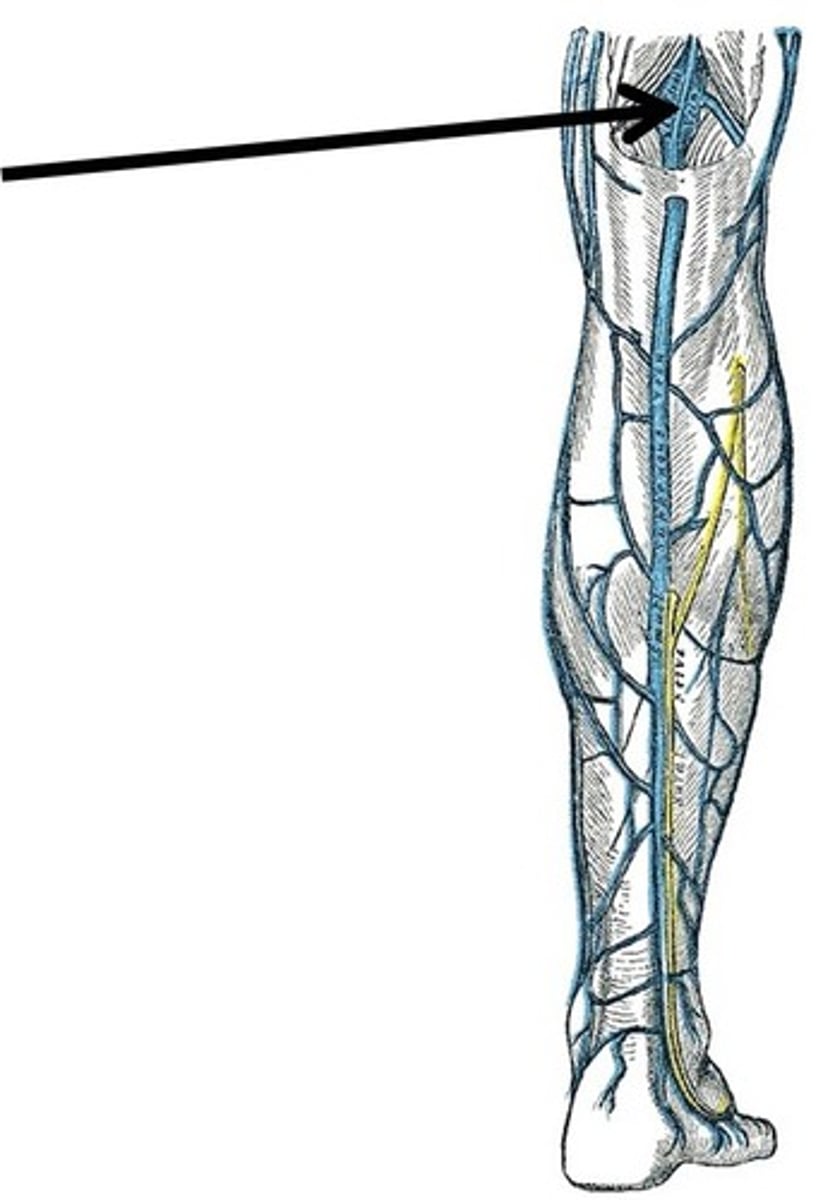

femoral vein

saphenous vein

longest vein in the body

popliteal vein

anterior tibial vein

posterior tibial vein